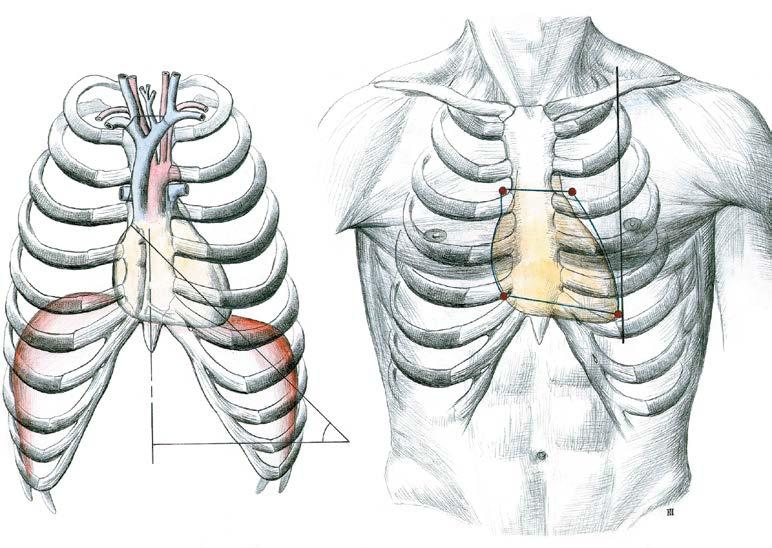

Srdce je uloženo v mediastinu, za sternem, svou jednou třetinou je vpravo od střední čáry, dvěma třetinami vlevo od střední čáry. Otisk srdce, prostřednictvím obalu srdce – perikardu – je patrný na obou plicích. Prostřednictvím perikardu nasedá srdce na bránici (obr. 5).

má tvar nepravidelného kužele s bazí obrácenou dozadu vzhůru a s hrotem směřujícím dopředu dolů a doleva; basis cordis – baze srdeční – je kraniální širší část, kde jsou uloženy předsíně srdeční a kde do předsíní vstupují velké žíly a z komor vystupují hlavní tepny –aorta a plicnice (obr. 7); apex cordis – hrot srdeční – zaobleného tvaru – je na komorové části srdce, směřuje doleva dolů vpřed a jeho úder může být hmatný vlevo v 5. mezižebří, těsně navnitř od medioklavikulární čáry (obr. 7).